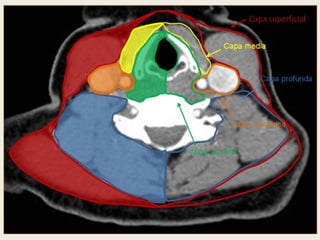

 Proyección del área de contacto de los espacios profundos del cuello suprahioideo sobre la base del cráneo. La

línea negra representa la inserción de la fascia faringobasilar, que delimita el espacio mucoso faríngeo, el cual se

relaciona con el agujero rasgado anterior (RA). A este nivel hay una pequeña área de contacto entre los espacios

mucoso y parafaríngeo preestiloideo (marcado en color negro). En color blanco se representa el espacio

masticador, en gris oscuro el espacio carotídeo o parafaríngeo retroestiloideo y en gris claro el espacio

parotídeo.

 Obsérvese que en el espacio masticador se encuentran el agujero redondo (AR), donde pasa la segunda rama del

trigémino (V2), y el foramen oval (FO), donde pasa la tercera rama del trigémino (V3). En el espacio carotídeo se

encuentra el agujero rasgado posterior, donde salen los pares craneales IX, X y XI. Se enfatiza el paso de los pares

craneales en dichos espacios, dada la importancia de la detección de una posible infiltración de un compartimiento

intracraneal a través de los agujeros de la base del cráneo en la estadificación de tumores de esta región.